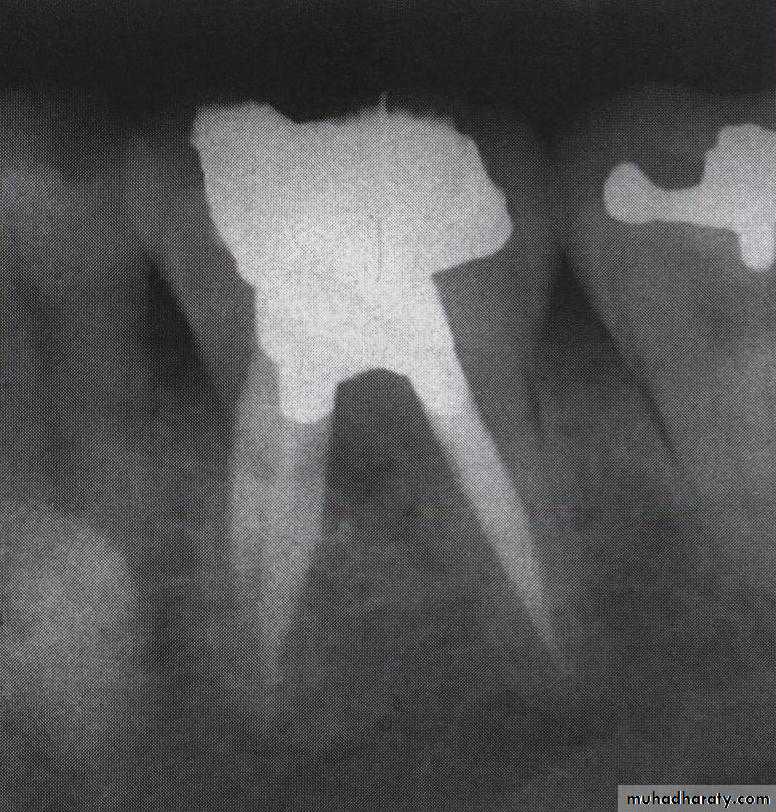

• 2- Furcation perforation

Treatment: immediate sealing using the suitable restorative material (MTA)Furcation repair using mineral trioxide aggregate (MTA)